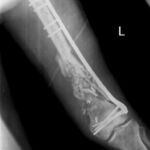

2.1. Учебная и клиническая база кафедры